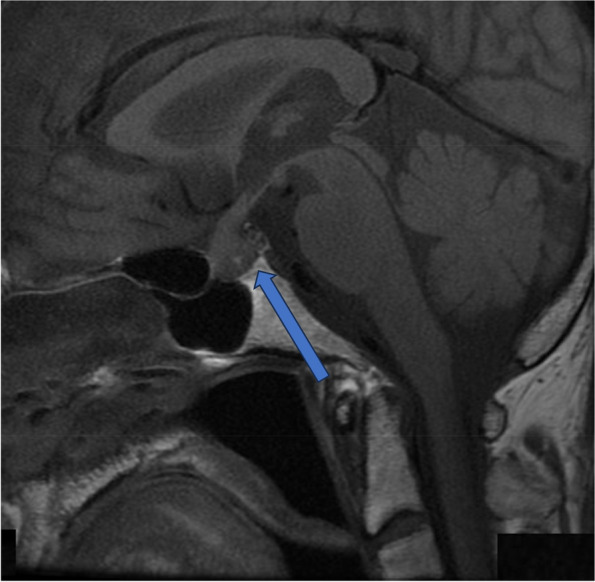

Fig. 2.

T1-weighted sagittal and T2- weighted coronal MRI of the brain (3rd day of admission). The arrow shows a mass-like lesion from the sella turcica to the suprasellar region and a thickened pituitary stalk. MRI, Magnetic resonance imaging